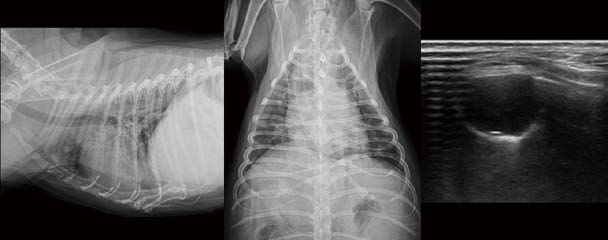

13살 수컷 Cocker spaniel이 기침, 호흡곤란으로 내원하였습니다. CRP 172.7 (0 15mg/dl ~) 확인되었고, 흉부방사선 검사에서 양쪽 전엽의 밀도가 약간 증가(특히 우측)되어 보입니다(A, B). 그러나 비만한 체형, 둥근 심음영, 최대 흡기 촬영이 되지 않은 점, Skin fold artifact 등으로 인해 좀 더 세밀한 판독은 어렵습니다. 폐초음파 검사를 실시했을 때, 왼쪽 전엽은 collapse되어 관찰되며(C), 오른쪽 전엽은 shred sign을 동반한 폐 침윤 소견이 일정 영역 이상 관찰됩니다(D). 오른쪽 전엽 주변 후방으로 소량의 B line이 관찰됩니다(E). C와 같은 lung collapse(atelectasis)는 폐엽 volume이 감소하고, 균질한 contour를 보이며, dynamic air bronchogram 없이 static air bronchogram 또는 공기 음영이 소실된 parallel-running bright lines만 관찰되게 됩니다.

이 환자에서 좌측 전엽은 기존 폐렴 병력으로 인한 atelectasis 가능성이 고려됩니다. D의 소견은 병적인 폐침윤 영역과 정상 폐 공기 음영의 irregular interface, 즉 shred sign을 동반한 폐렴의 전형적인 영상입니다. 실시간으로 보면 dynamic air bronchogram이 관찰됩니다. 이렇게 현재 진행형인 폐의 병적 변화 주변으로는 focal parapneumonic pulmonary edema도 함께 관찰될 수 있습니다(E). 다만, shred line으로부터 우연히 발생하는 ring-down artifact와 parapneumonic pulmonary edema는 감별해야 합니다. 이렇게 폐초음파는 병변의 양상을 파악하고, chronicity, severity 정도를 판단함으로써, 환자의 치료 방향을 제시하고, 개선/악화/변화 없음 등의 모니터링에 유용하게 사용될 수 있습니다. 환자는 보호자님의 요청으로 추가적인 검사 없이 일반적인 폐렴에 준한 치료를 진행하였고, 대부분 개선되었습니다.